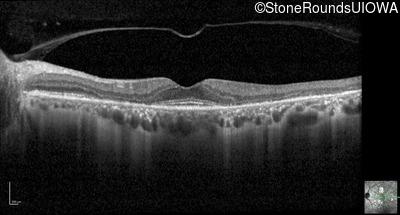

Optical Coherence Tomography - Left - 20/20 -1

Exemplar / OCT Stack

OCT Stack